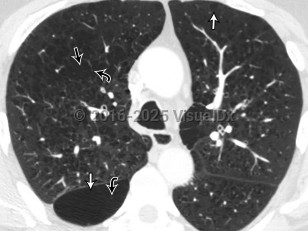

Chronic obstructive pulmonary disease (COPD) is a preventable and treatable condition with both pulmonary and extrapulmonary effects. Despite this, it is the third leading cause of death worldwide. COPD is characterized by chronic airflow obstruction that is not fully reversible. The disease is usually progressive and due to an abnormal inflammatory response in the lungs. Extrapulmonary manifestations include systemic inflammation, weight loss / nutritional deficiency, anemia, skeletal muscle dysfunction, and an increased risk for cardiovascular comorbidities.

COPD due to cigarette smoke exposure leads to more severe emphysema and more rapid decline in lung function compared with COPD from biomass exposure. The latter presents with distinctive airway wall thickening and sees lung function improve from the use of bronchodilators. The number of symptoms, exacerbations, and hospitalizations is higher in patients with asthma leading to COPD compared with patients with smoking-associated COPD, although, paradoxically, the asthma-associated mortality rate is lower.